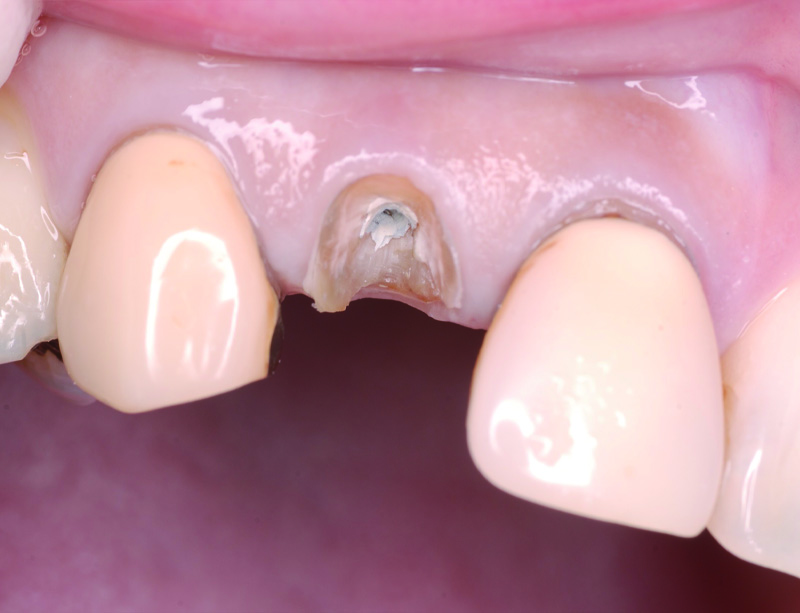

術前の状態です。右上中切歯の被せ物が合っていないことがわかります。また周りの歯の樹脂も劣化が認められます。

被せ物を外すとう蝕が認められました。

土台外すとさらに根管の中にもう蝕が認められました。

残っている歯の量が少ないため、根管治療後に部分矯正にて歯を引っ張り上げる(矯正的挺出)こととしました。

その際は表には仮歯をつけて見た目の確保を行います。

矯正的挺出が終わった状態です。歯とともに歯肉と骨も一緒に引っ張り上げられるので、

手術(歯冠長延長術)によって歯肉と骨を整形し、健康な歯の量を確保します。

歯冠長延長術を行ったところです。

その後土台を築造し、型取りを行います。

右上中切歯にセラミッククラウンを装着して、周りの歯の樹脂もやり替えを行いました。